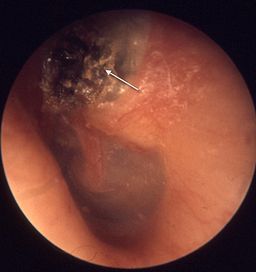

Cholesteatoma

• Suppurative labyrinthitis; usually spread into bony labyrinth from invading cholesteatoma (see cholesteatoma image to the right)